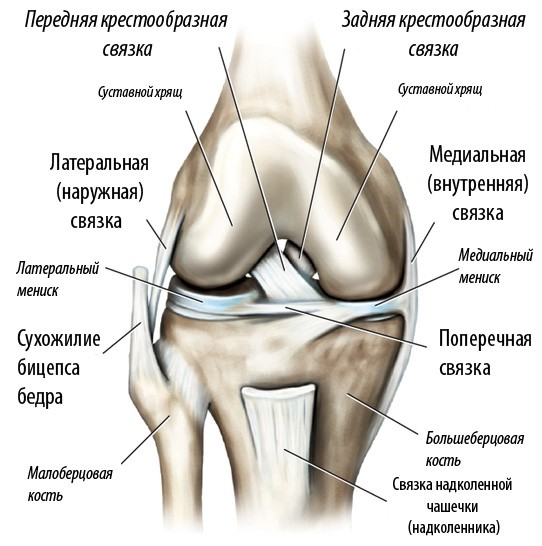

Повреждения крестообразных связок коленного сустава

Передняя крестообразная связка (ПКС) — главный стабилизатор колена, который удерживает голень от смещения кпереди.

При повреждении (разрыве) передней крестообразной связки возникает патологическая передне-задняя подвижность, что сопровождается ощущениями неустойчивости и болями в коленном суставе.

Причиной разрыва передней крестообразной связки чаще всего является спортивная или бытовая травма, связанная с вращением бедра относительно голени — разворот корпуса при фиксированной стопе. Наиболее характерным это повреждение является для травм, полученных при падении на горных лыжах и занятиях контактными и игровыми видами спорта (борьба, футбол, хоккей, волейбол и т. д.).

Для разрыва передней крестообразной связки характерен выраженный болевой синдром в момент получения травмы, возникновение отека коленного сустава в первые сутки. Нередко первые несколько недель пациент не отмечает ощущений неустойчивости в коленном суставе, однако в дальнейшем они нарастают, проявляясь сначала при спортивных, а потом и при повседневных бытовых нагрузках. В случае если пациент с повреждением передней крестообразной связки длительно не получает необходимого лечения, патологическая подвижность в суставе приводит к развитию остеоартроза и необратимых изменений хрящевого покрова коленного сустава.

Диагностика. Разрыв передней крестообразной связки подтверждается результатами магнитно-резонансной томографии (МРТ) коленного сустава. Рентгенография не является информативным методом исследования при разрыве ПКС, поскольку мягкие ткани, связки и хрящевые структуры не видны на рентгеновских снимках. На МРТ возможно выявить не только признаки повреждения ПКС, но и сопутствующие травмы менисков и хрящевого покрова сустава.